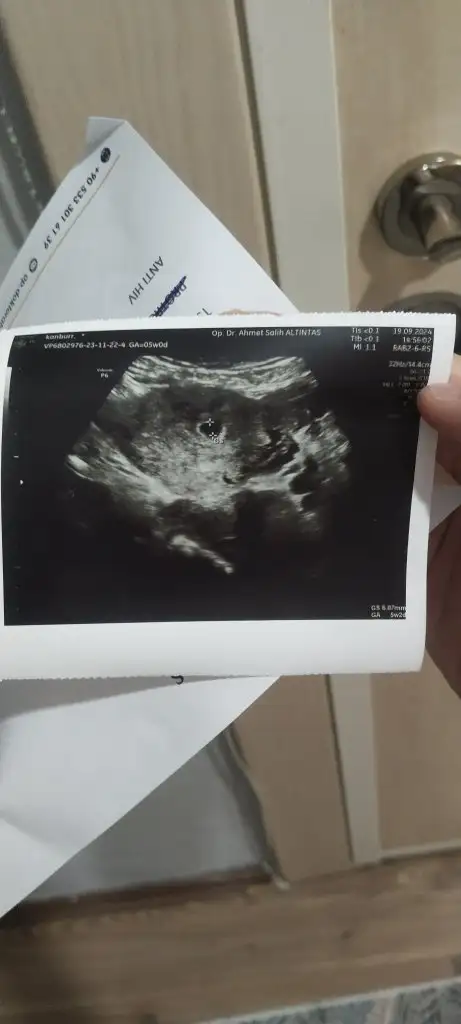

Cok güzel haberrKızlar keseyi gördük çok şükür6+1 ölçtü doktor henüz bebek yok ama yolk sac oluşmaya başlamış dedi. 10 gün sonra kalp atışı için çağırdı

Canım tebrik ederim kese boyutunu söyledi mi? Yolk sac oluşumu falanKizlar ben de keseyi gördüm bugün çok şükür 5+2 ölctü. Dış gebelik değil dedi yerleştiği konum iyi dedi kanama alanı görmüyorum dedi 2 hafta sonra kalp atışı için çağırdı

Ne güzel haber artık kalp atışını bekleyeceğizKizlar ben de keseyi gördüm bugün çok şükür 5+2 ölctü. Dış gebelik değil dedi yerleştiği konum iyi dedi kanama alanı görmüyorum dedi 2 hafta sonra kalp atışı için çağırdı

Boyutu ölctü yolk saç falan filan demediCanım tebrik ederim kese boyutunu söyledi mi? Yolk sac oluşumu falan

Hadi gözünüz aydınBoyutu ölctü yolk saç falan filan demedi

Altta GS yazan yer kese boyunuzBoyutu ölctü yolk saç falan filan demedi